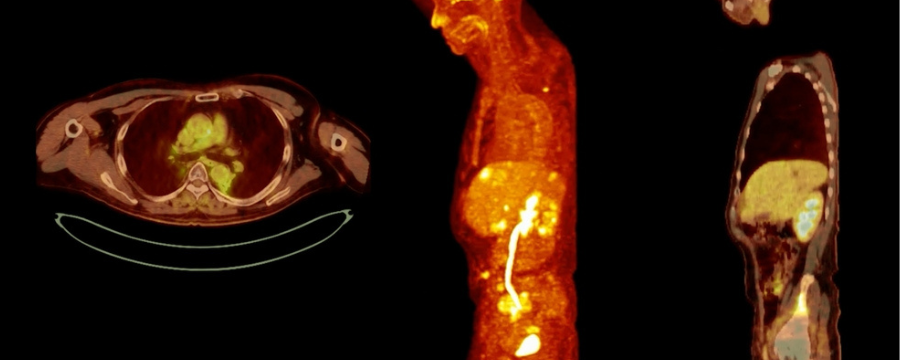

La tomografía por emisión de positrones, también conocida como PET, es una técnica de obtención de imágenes que permite visualizar y medir los procesos metabólicos en el cuerpo. Esto puede ser interesante para aquellos órganos o tejidos de los que se sospeche que puede haber células cancerosas o daños que impiden su adecuado funcionamiento.

En el campo de la oncología, la tomografía por emisión de positrones es muy útil. El escáner crea imágenes tridimensionales con gran detalle para identificar un cáncer, inflamación o masa extraña. No obstante, la tomografía por emisión de positrones también se emplea, en ocasiones, en el área de cardiología de los hospitales, con el fin de identificar la epilepsia o la enfermedad de Alzheimer para iniciar un tratamiento temprano.